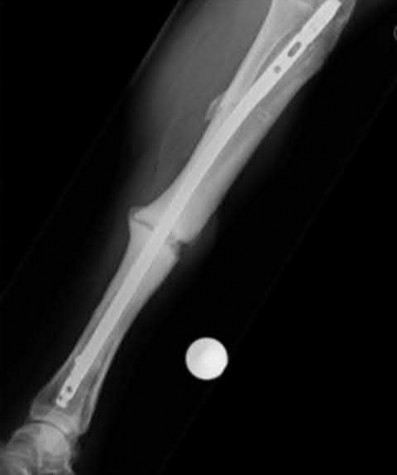

Question 17

A 32-year-old male sustains a closed tibia fracture and develops intense leg pain out of proportion to the injury. You suspect acute compartment syndrome.

Which of the following pressure parameters is considered the most reliable threshold indication for performing a four-compartment fasciotomy?

Explanation

The differential pressure (Delta P) is universally recognized as more reliable than absolute compartment pressure for diagnosing acute compartment syndrome. A Delta P is calculated by subtracting the intracompartmental pressure from the patient's diastolic blood pressure. A Delta P of less than 30 mmHg represents inadequate tissue perfusion pressure and is an absolute indication for emergency fasciotomy.